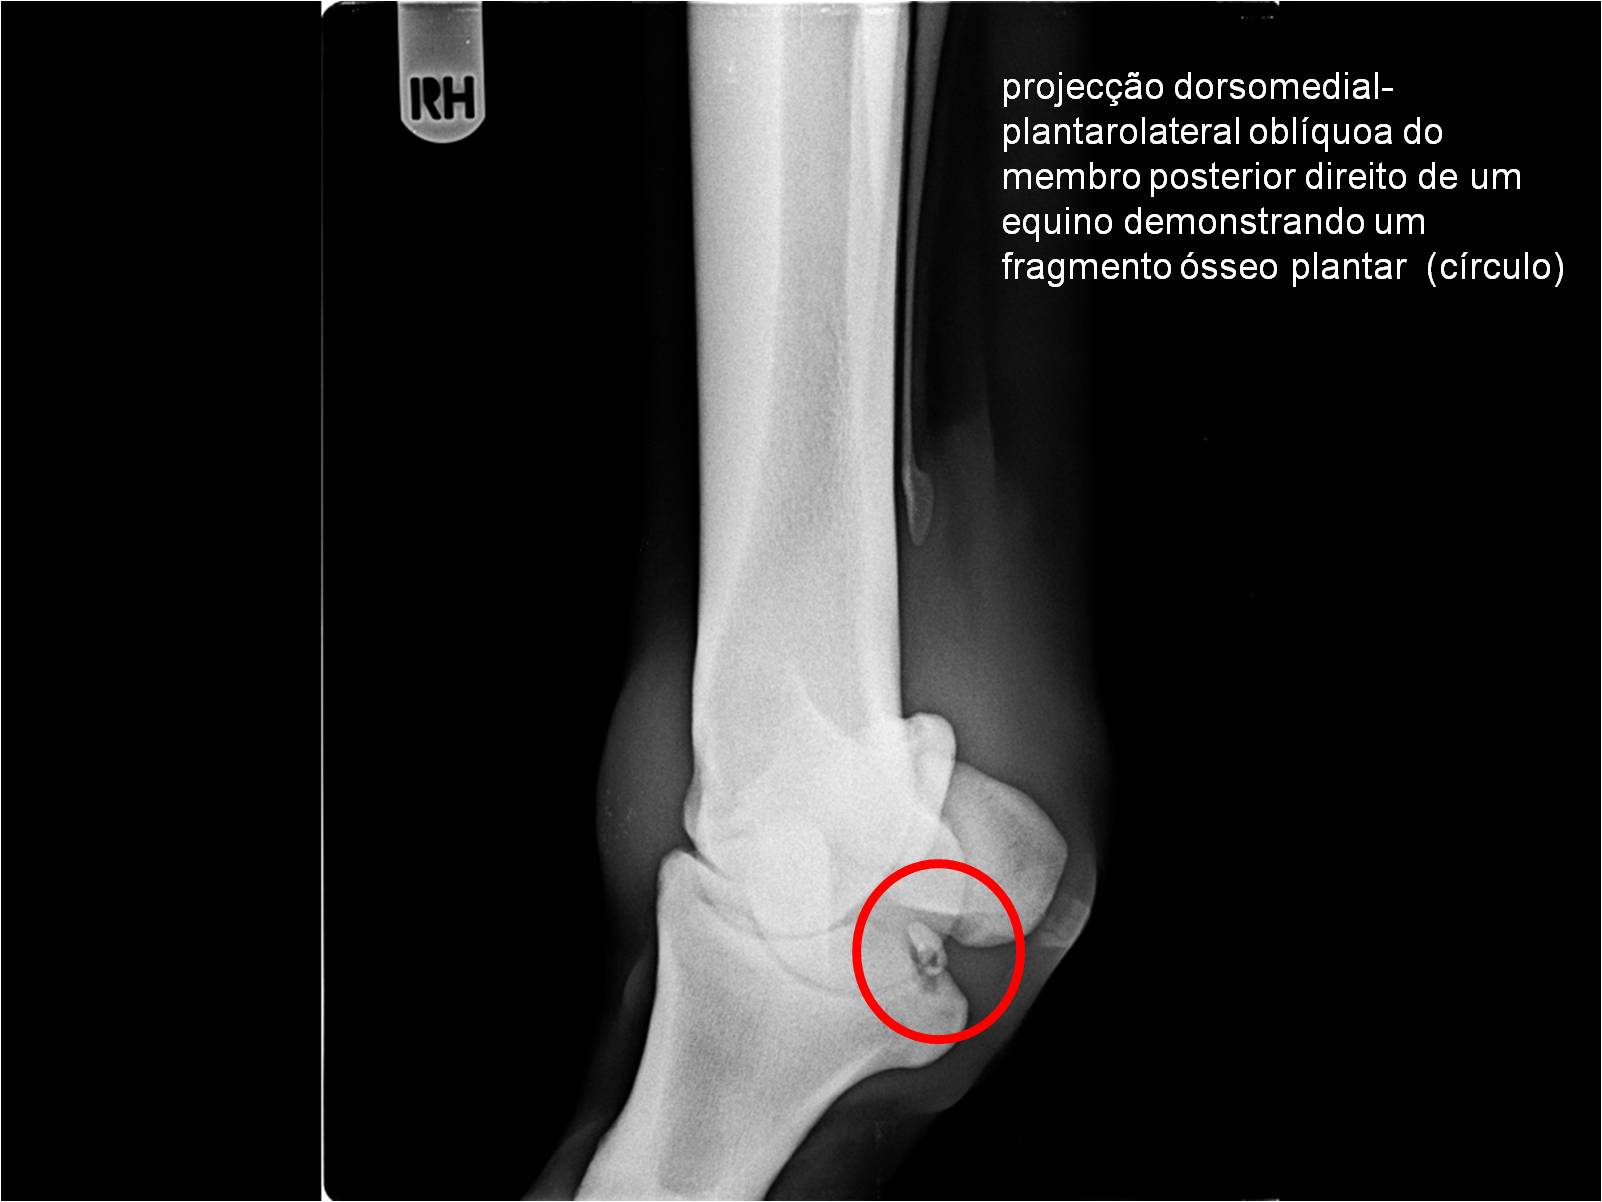

Publisher: Universidade de Évora

Abstract: O relatório de estágio encontra-se estruturado em três partes distintas. A primeira parte faz a caracterização das infraestruturas e funcionamento do Hospital Veterinário de Equinos de Lüsche, Oldenburg, Alemanha, assim como a análise casuística dos casos clínicos acompanhados durante os 6 meses de estágio. A segunda parte consiste de uma revisão bibliográfica sobre quistos do osso subcondral em equinos. Por fim, a terceira parte consta da apresentação e discussão de um caso clínico, nomeadamente o diagnóstico e acompanhamento imagiológico, por ressonância magnética, de um quisto subcondral na terceira falange num cavalo adulto; ### Abstract Equine Practice- Subcondral bone cyst of the third phalanx This internship report is divided in three parts. The first part characterizes the infrastructure and function of the Equine Hospital Lüsche, Oldenburg, Germany, as well as the casuistic of the clinical cases accompanied during the 6 month internship. The second part consists in a bibliographic review of cystic lesions of the subchondral bone in equines. The third part consists in a case report, the diagnostic and imagiological accompaniment, by use of magnetic resonance imaging, of a subchondral bone cyst in the distal phalanx of an adult equine.